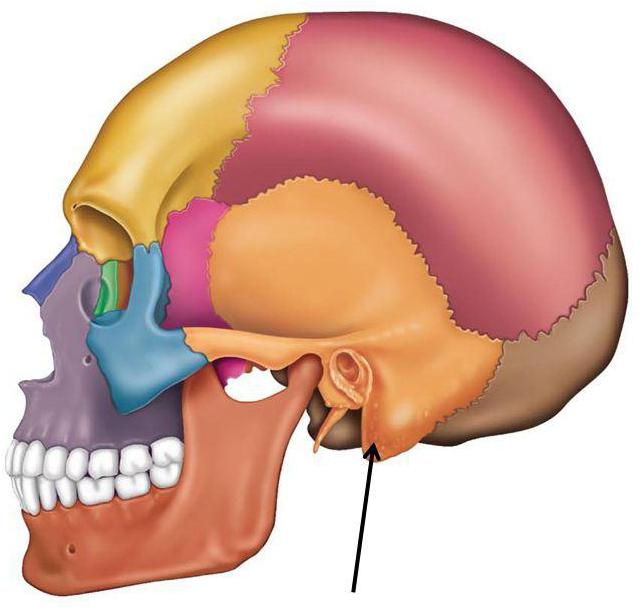

Скронева кістка складається з трьох областей: лускатої, барабанної та кам’янистій. Луската область утворює бічні стінки черепа; барабанна частина – елемент, який оточує з усіх боків слуховий канал;

кам’яниста частина зовні виглядає як піраміда і виконує функцію вмістилища для середнього і внутрішнього вуха, крізь яку проходять також кровоносні судини. Піраміда включає в себе три поверхні – передню, задню і нижню. Нижня область утворює соскоподібний відросток.

Що таке мастоїдит та соскоподібний відросток скроневої кістки – визначення захворювання

Соскоподібний відросток являє собою виступ конічної форми, розташований позаду вуха. Внутрішня будова соскоподібного відростка – це сукупність кісткових порожнин, заповнених повітрям і сполучених з середнім вухом (з барабанною порожниною) через соскоподібний печеру. Печера (антрум) – найбільша клітина соскоподібного відростка. До

Структура відростка індивідуальна для кожної людини. Розрізняють три типу його будови. Пневматична будова – соскоподібний відросток складається з великих осередків, заповнених повітрям. Диплоэтическое будова – структура являє собою дрібні комірки, заповнені кістковим мозком. Склеротическое будова – комірчаста структура дуже слабо виражена.